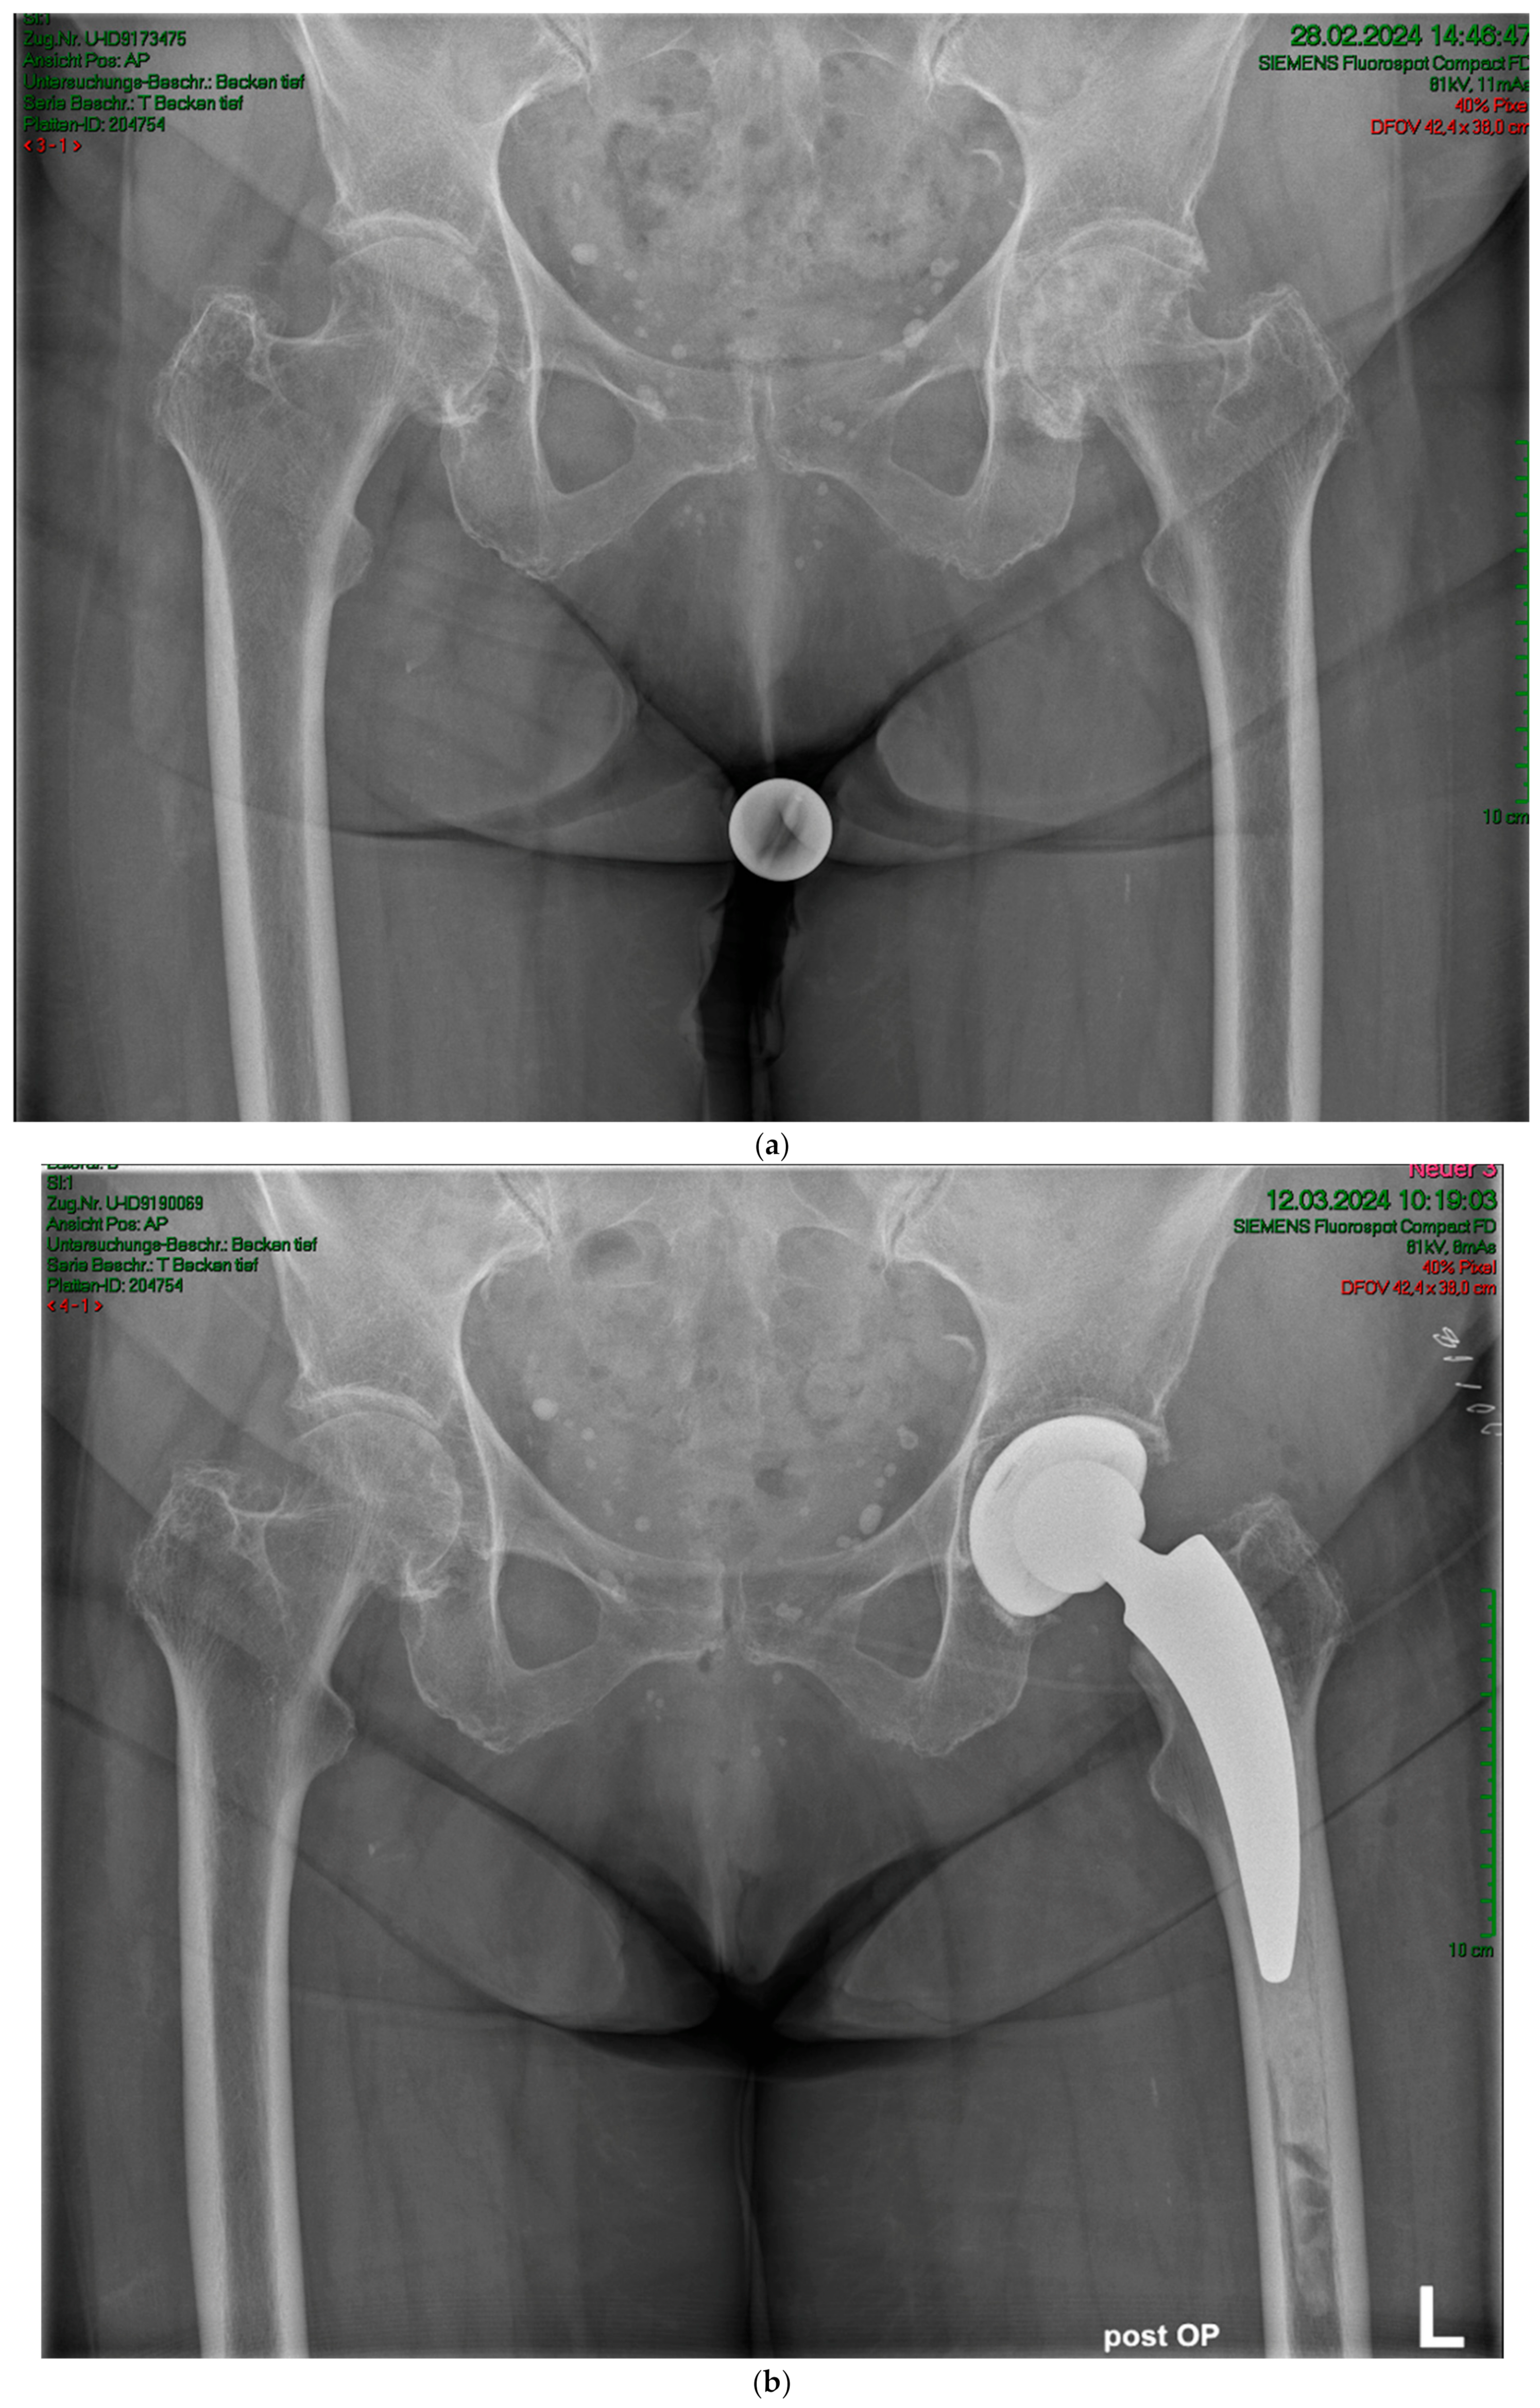

(a) Case #3: Osteoarthritis, female, 81 years old, preoperative planning. (b) Correct implant position 1 week postoperatively. Homogeneous cement mantle.